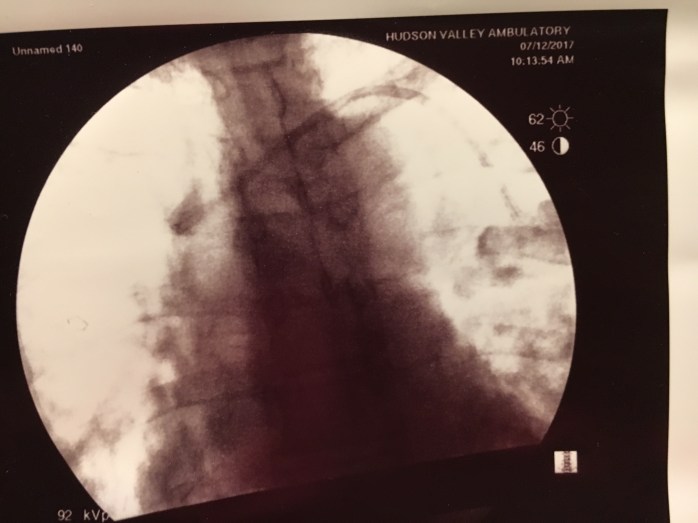

That same week, my son contracted a bad cold and cough.  I tried to stay away from him but on St. Patrick’s Day, I woke up feeling like garbage.  I had originally planned to march in the St. Patrick’s Day Parade in NYC with the LAOH.  Nope.  I stayed home and watched the parade on TV.  The following day I was feeling worse.  I went to Mass as I had been assigned to lector that day.  I barely made it through the closing announcements I was so short of breath.  I made an appointment to see my doctor on Monday the 19th.  I hadn’t slept because I had been up coughing all night.  The over the counter cough and cold medicine was doing nothing for me and my lungs sounded like the “Snap, Crackle, and Pop” of Rice Krispies in milk (or Pop Rocks in your mouth).  My doctor put me on a Z Pack and low dose steroids.  I told him that the WTC doctor told me that my breathing issues may not all be physical.  He looked surprised and asked if the doctor actually knew my medical history!  By Friday March 23rd, I was still feeling miserable.  Any physical activity was draining.  I was coughing a lot.  After every cough attack, I would look at the Fitbit on my wrist and my heart rate would be hovering around 90.  The Fitbit read “Fat Burn.” Who knew coughing was a work out?  I went back to my doctor.  He prescribed Levaquin and doubled the steroid dosage.  On Palm Sunday, I was unable to go to Mass.    Charles stopped and picked up Palms for me and my friend Patrick came and brought me Holy Communion.  I stayed on my couch in my pajamas all day.  Even getting dressed was a chore. In the evening, I took a hot bath hoping it would help.  I got out of the tub and felt even worse.  Charles wanted to take me to the Emergency Room.  I used my nebulizer instead and once my heart rate slowed, I tried to fall asleep sitting up on the couch.  I had been attempting to sleep sitting upright all week.  As I was unable to sleep, I decided to color in my “Adult Coloring Book.” This became difficult because I kept getting cramps in my hands (and feet).  On Monday the 26th, I was still feeling shitty  and short of breath.  I decided to use my nebulizer again.  Whilst using my nebulizer, my hands and feet went numb and I got dizzy.  I walked into my kitchen and leaned over my counter.  When I went to stand up, I temporarily blacked out.  My arms and legs just gave out and I saw black.  Thankfully Charles was there to catch me.  We called my doctor again.  Back to his office.  He took one look at me and sent me to the Emergency Room so that additional tests (Chest X-ray) could be done and so that I could get some IV steroids.  (This time I is was in cubicle 9). IMG_7519

It was bizarre.  My doctor called with some orders and the testing was done.  An IV was started and a bunch of blood work was done, including tests to see if I had a blood infection (though these results would not be available for at least 48-72 hours).  A nebulizer treatment was also done.  The Chest X-Ray was negative (no pneumonia) as was the flu test.  I  did NOT have a fever.  My temperature hovered around 97.8.  The ER doctor didn’t think my wheezing sounded too bad and considered sending me home.  I explained that my asthma issues didn’t always present with wheezing.  It was worse for me when my chest was so tight there was no wheezing.  He asked if I wanted to be admitted to the hospital! I’m not a doctor.  What did my doctor say???!! The decision was ultimately made to admit me for a couple days so that I may receive high dose IV steroids.  I was brought up to a room.  More testing.  A Chest CT.  Also clear.  I didn’t sleep at all Monday night.  Breathing treatments every four hours and too many steroids pumping through my system.